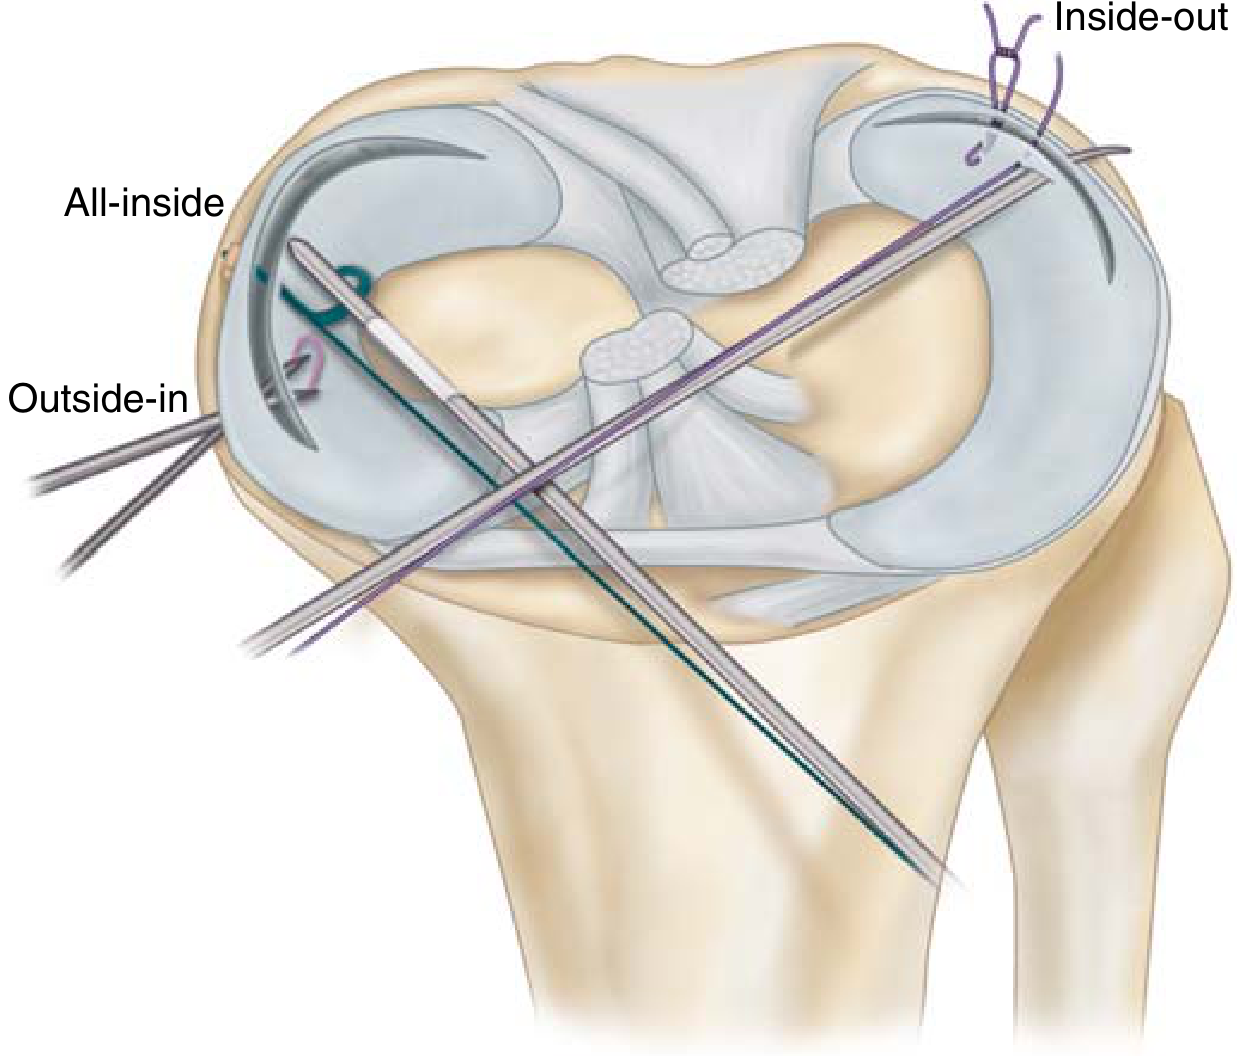

Surgical Techniques

Meniscal repair techniques — outside-in, inside-out, and all-inside approaches

Meniscal repair techniques: outside-in, inside-out (gold standard), all-inside (Miller's Review of Orthopaedics)

TechniqueDescriptionNotes

OpenDirect suture via open incisionRarely used today

Outside-inNeedles passed through skin into jointGood for anterior tears

Inside-outCannulas passed through portals; sutures tied externallyGold standard — vertical mattress sutures

All-insideEntirely intra-articular using implant devicesMost popular due to ease of use; latest generation allows tensioning

Nerve protection during repair:

• Medial repairs → protect saphenous nerve branches (anterior to semitendinosus/gracilis, posterior to sartorius)

• Lateral repairs → protect peroneal nerve (posterior to biceps femoris)